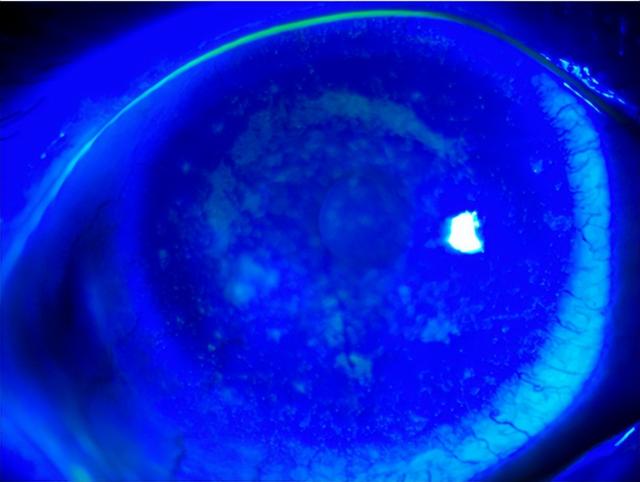

医生检查后发现,小静的眼角膜不仅出现了水肿、缺氧的情况,还“爬满”了大量新生血管;双眼睑缘红肿,结膜充血;睑板腺开口部分堵塞,油脂污浊;角膜散在大小不等的白色病灶,荧光素染色可见弥漫染色。

据悉,眼睛角膜上是没有血管的。小静角膜上“爬满”新生血管是由于组织发生炎症,缺血缺氧导致了血管内皮生长因子的大量释放,然后产生了这些坏的血管。这些坏的血管可以从角膜边缘开始,蔓延到角膜中央,角膜新生血管有时会伴有角膜上皮细胞的脱落,甚至是角膜溃疡。

因此,一旦产生了这些新生血管可能会引起很严重的后果,甚至造成失明。